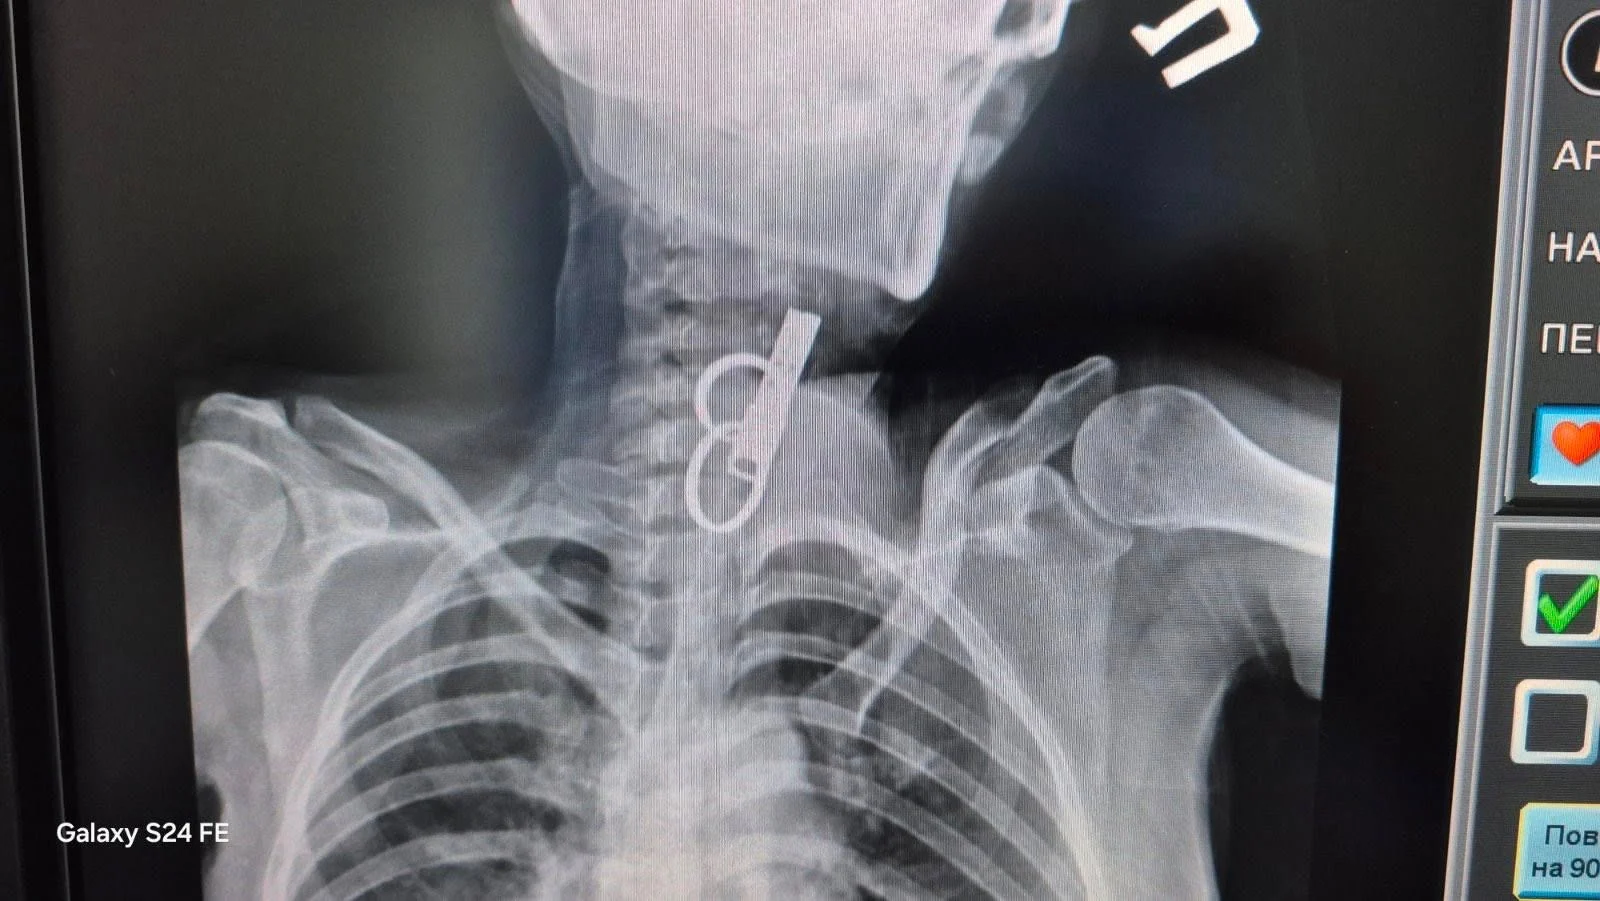

«Це дуже показовий випадок, що нам вдалося її врятувати. Як свідчить практика, переважно такі хворі гинуть. Спочатку ми не могли зрозуміти, що застрягло у стравоході. Це були якісь металеві кільця, які стояли зверху, а далі було ще якесь чужорідне тіло. Я здогадався, що це може бути ключ від дверей і почав його обережно витягувати», – розповів Олександр Садовий.

З’ясувалося, що ключ жінка проковтнула, щоб не віддати його родичам і, щоб вони не мали доступ до її помешкання. Лікар додає, що в обласну лікарню у Тернополі не ризикнули везти пацієнтку, оскільки її вже доставили в стані шоку, то жінку просто б не довезли. Рішення про операцію приймали за лічені хвилини.